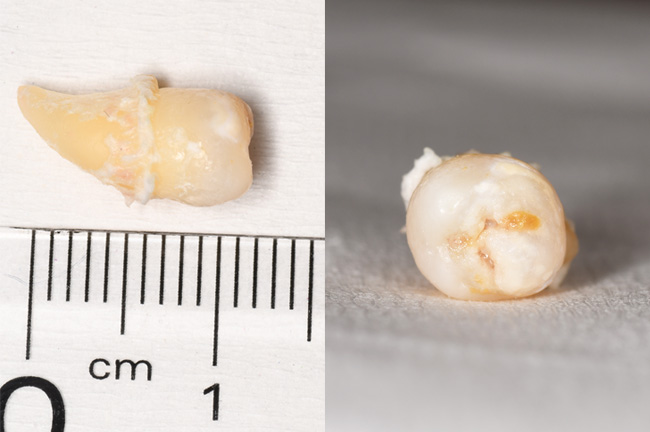

CASE 19

抜歯前:レントゲン

抜歯前:お口の中

抜去歯

抜去歯:根の形

基本情報

| 年齢・性別 | 20代・男性 |

|---|---|

| 主訴 | 主訴:痛みはないが虫歯になっているため抜歯したい 部位:右上の8番 |

| 治療内容 | 麻酔をし、歯を脱臼させ抜歯を行った。 |

| 治療期間 | 30分 |

| 治療費 | 約3,000円(保険診療3割負担) (2024年7月現在) |

| リスク・副作用 | ・上顎洞と交通し、空気や水が漏れる可能性がある。 ・腫れや痛み、熱がでる可能性がある。 ・当日は飲酒や激しい運動などの血行が良くなる行動を避けていただく。 ・口が開けづらくなる可能性がある。 ・麻酔が2、3時間効いているので、食事に充分注意していただく必要がある。 ・ドライソケットになる可能性がある。 |

| 治療方針 | 親知らずを抜くことで、口腔内の虫歯のリスクを下げる。 |

| 担当者所見 | 抜歯後、抜歯窩に汚れが溜まりやすく、細菌感染リスクを下げるため、柔らかい歯ブラシで優しく磨きマウスウォッシュで口腔内を清潔に保ちましょう。 |